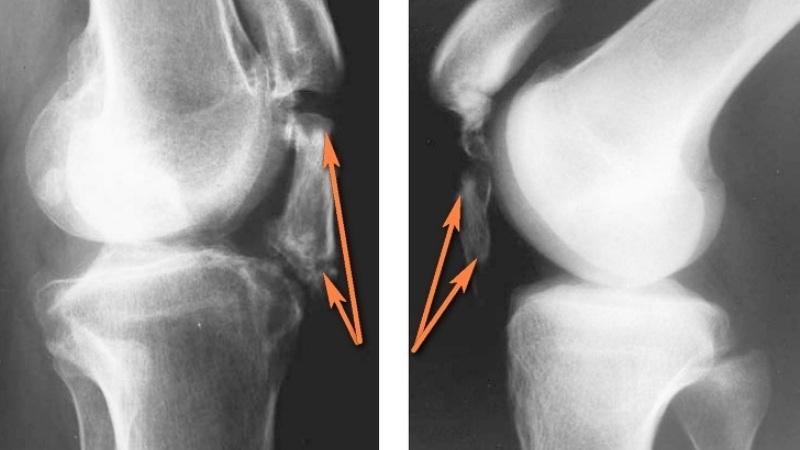

Перелом можно определить, основываясь на явных клинических признаках, а также собирая анамнез. Важно также провести опрос о предыдущих наблюдениях. После этого пациента направляют на ультразвуковое и рентгенологическое обследование. Не будет лишним также пройти компьютерную томографию.

Для подтверждения перелома седалищной кости обычно проводят рентгенографию. В некоторых случаях может потребоваться МРТ или КТ для более детального изучения повреждений и оценки состояния окружающих тканей.